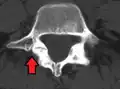

Degenerative spondylolisthesis at L5-S1.

(A) CT sagittal view of a low grade slip.

(B) Lateral radiograph pre-operative intervention.

(C) Surgically treated with L5–S1 decompression, instrumented fusion and placement of an interbody graft between L5 and S1.